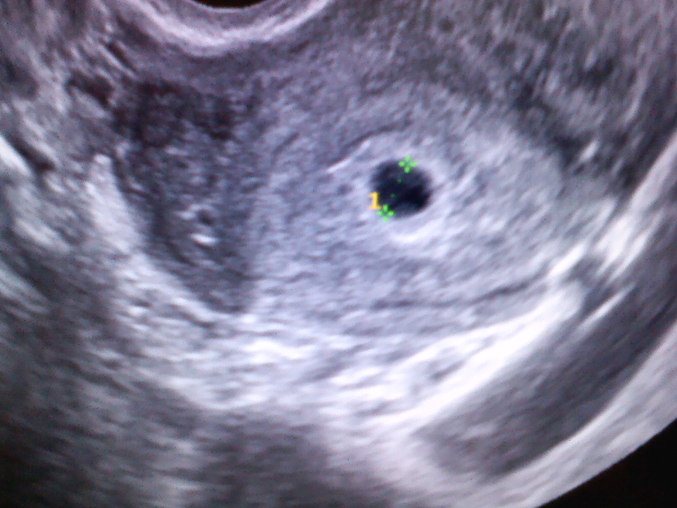

На этом фото второго ПЯ не видно, но вот в этом ПЯ мне видится 2 эмбриончика - один сверху, второй снизу :).. Но я не врач конечно, на след.узи вам уже точно скажут. Было бы прикольно, если двойняшки :)